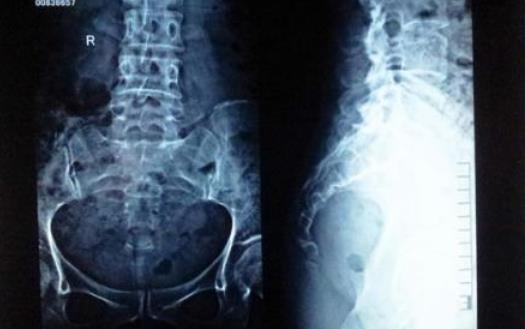

尾骨其实就是人类的“尾巴”,随着人类的进化,尾巴的作用越来越小,最终“退化”到如今的结构,看起来像是三角形。由于生理结构的不同,女性尾骨比男性的更小、更低一些,所受压力更大,因而女性更容易出现尾骨疼痛。

除了慢性劳损,外伤、退行性病变、盆腔疾病甚至肿瘤等原因都可能引发尾骨疼痛。坦言,针对长期劳损甚至韧带钙化引起的尾椎疼痛,传统的药物治疗、热敷等效果往往不佳,原因是患处解剖位置比较特殊,患者比较难依从。借助冲击波治疗尾椎痛,因为治疗时间短,患者依从性提高,效果缓解十分明显。尾椎疼痛比较严重时,可以尝试使用中间镂空的坐垫,避免尾骨受到椅面挤压而疼痛加剧。